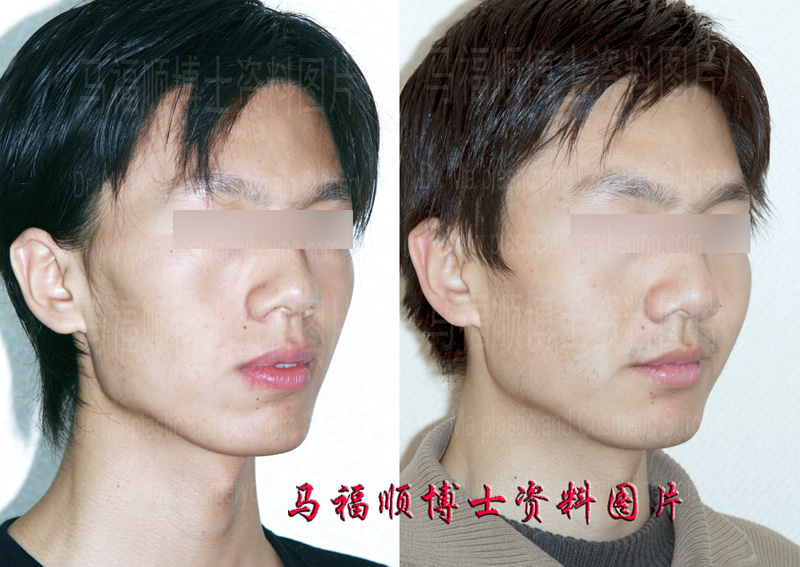

The handsome boy in this page had a bony face. On top of that he also had a protrusion mouth. His facial outline in profile is quite rough and irregular. He was also bothered with the parted lips in relax. He always tried to forcefully close his mouth hiding his teeth in attending important gatherings and in facing other people. However a prolonged forceful mouth closure would make himself uncomfortable on his lips. So he came and saw Dr. Ma for help. Upon the first contact Dr. Me believed his protrusion was not very serious and tried to convince him to forget the idea of surgery. But he insisted to do the surgery and told Dr. Ma that others hardly understand his psychological suffering from the condition. At the end Dr. Ma was convinced and a protrusion mouth plastic surgery was performed to setback the front part of his upper and lower jaws according to his degree of protrusion. When he came back for a follow-up later on he was satisfied with the after surgery result and told Dr. Ma that he never bothered to deliberately worry if his teeth were shown any more since then.

After surgery the protruded mouth was pushed back. The facial outline in profile is smoother.

The lips can meet each other in relax after the protrusion correction surgery. The relationship between the lips and the chin are more natural.

The most obvious change in different groups of the before and after surgery comparison photos in this page is that the face of this handsome boy is not bony any more. Though this change could be caused by weight gain (as a matter of fact he didn’t gain weight after surgery), the dominate fact contributed to this change is the correction of the mouth protrusion. Because of the different aesthetic taste on face contour some people like bony face, while the others want a rounded one. This boy didn’t like bony face. So he insisted to get rid of the protrusion and felt happy with his post surgery result.

Another important change in this boys face is that his lips can meet each other in relax. In Dr. Ma’s opinion the parted lips and exposed teeth are the most bothering problems for protrusion mouth candidates. For people without mouth protrusion the teeth may show when smile. However for people with mouth protrusion the teeth may always show no matter happy or angry. Exposed teeth without the cooperation of facial express can be quite unnatural. This is the reason why so many mouth protrusion candidates insists on doing the surgery for a change. In another words the protrusion correction surgery dose not only change the look of the candidates but also relieve their psychological burden helping them gain confidence.